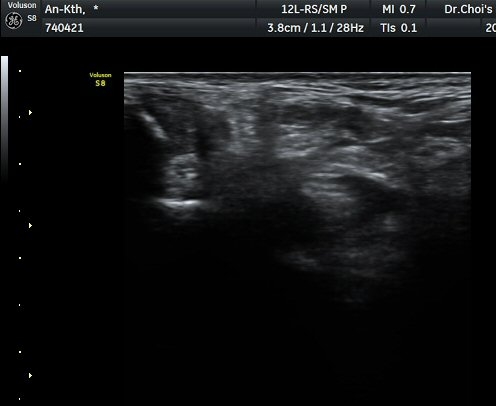

ÃÊÀ½ÆÄ ¼Ò°ß

¹ß¸ñ ³»Ãø Ⱦ´Ü¸é°Ë»ç¿¡¼­ ±ä¾öÁö±¼°î°Ç(FHL)ÀÇ ºÎÁ¾°ú °Ç ÁÖÀ§ ¼ö¾×Àú·ù°¡

°üÂûµÈ´Ù(±×¸² 1, 2, 3). ±ä¾öÀÚ±¼°î°Ç Á¾´Ü¸é°Ë»ç¿¡¼­ ±ä¾öÁö±¼°î°ÇÀÇ ºÎÁ¾°ú